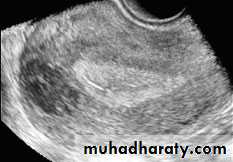

Rupture of hemorrhagic ovarian cyst:

Transabdominal scanned image

• Rupture of hemorrhagic ovarian cyst:

Transvaginal scanned image